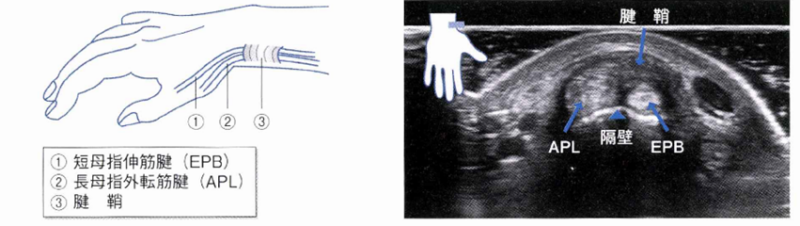

手関節僥側(親指側)の背側(手の甲側)区画の腱鞘炎ですが、腱鞘内で長母指外転筋腱(APL)と短母指伸筋腱(EPB)の間に隔壁が存在することがあり、その場合に腱鞘内の断面積が小さくなるため炎症をより起こしやすいと考えられています。

手関節の撓側側(親指の付け根のあたり)の圧痛とフィンケルシュタインテスト陽性(検者が母指を尺側に牽引したときに疾痛が誘発される)で診断しています。疾痛が強い症例には,エコーにて炎症(血流)の有無を確認できます。

腱鞘の部位に血流(炎症所見)を認めている。↓